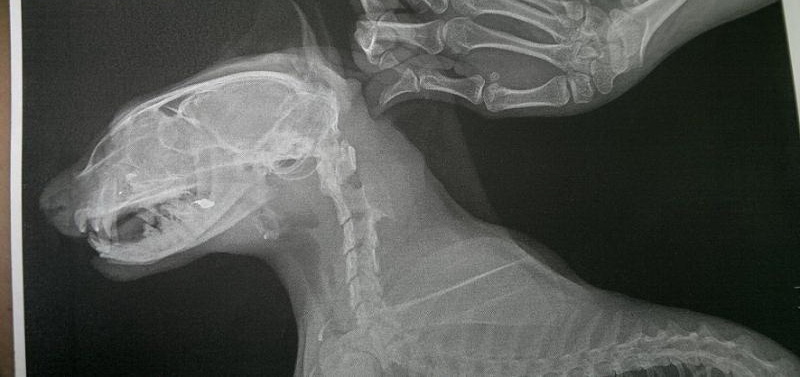

По предварительным данным- удар пришелся в голову, разбита носька, сломана челюсть, в легких все хлюпает... Ему вставили в нос трубку, провели противошоковую терапию..Если до вечера состояние станет более менее- повезут в ЦВК на рентген, где будет ясен точный диагноз и будет решаться вопрос о операции.Ребята, очень актуальна финансовая помощь! У кого есть возможность, помогите, пожалуйста